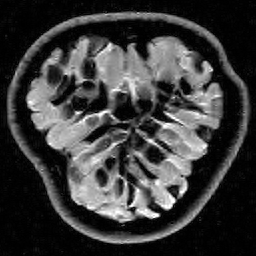

Hence both and should recover equally well. In the top row of Figure 1 we present the result of the flip test for a Gaussian random matrix. As is evident, the reconstructions and are comparable, thus indicating the RIP.

Having considered type II problems, let us now examine the flip test for a type I problem. As discussed, in applications such as MRI, X-ray CT, radio interferometry, etc, the matrix is imposed by the physical sensing device and arises from subsampling the rows of the DFT matrix .111In actual fact, the sensing device takes measurements of the continuous Fourier transform of a function . As discussed in BAACHGSCS ; BAGSAIEP , modelling continuous Fourier measurements as discrete Fourier measurements can lead to inferior reconstructions, and worse, inverse crimes. To avoid this, one must consider an infinite-dimensional compressed sensing approach, as in (2). See AHPRBreaking ; BAGSAIEP for details, as well as PruessmannUnserMRIFast for implementation in MRI. However, for simplicity, we shall continue to work with the finite-dimensional model in the remainder of this paper. Whilst one often has some freedom to choose which rows to sample (corresponding to selecting particular frequencies at which to take measurements), one cannot change the matrix .

It is well known that in order to ensure a good reconstruction, one cannot subsample the DFT uniformly at random (recall that the sparsifying transform is a wavelet basis), but rather one must sample randomly according to an appropriate nonuniform density AHPRBreaking ; Candes_Romberg ; Lustig ; WangAcre . See the bottom left panel of Figure 1 for an example of a typical density. As can be seen in the next panel, by doing so one achieves a great recovery. However, the result of the flip test in the bottom right panel clearly demonstrates that the matrix does not satisfy an RIP. In particular, the ordering of the wavelet coefficients plays a crucial role in the reconstruction quality. To explain this, and in particular, the high-quality reconstruction seen in the unflipped case, one evidently requires a new analytical framework.

Note that the flip test in Figure 1 also highlights another important phenomenon: namely, the effectiveness of the subsampling strategy depends on the sparsity structure of the image. In particular, two images with the same total sparsity (the original and the flipped ) result in wildly different errors when the same sampling pattern is used. Thus we conclude that there is no one optimal sampling strategy for all sparse vectors of wavelet coefficients.

The estimate (12) both agrees with the conclusion of the flip test in Figure 1 and explains the results seen. Flipping the wavelet coefficients changes the local sparsities . Therefore to recover the flipped image to the same accuracy as the unflipped image, (12) asserts that one must change the local numbers of measurements . But in Figure 1 the same sampling pattern was used in both cases, thereby leading to the worse reconstruction in the flipped case. Note that (12) also highlights why the optimal sampling pattern must depend on the image, and specifically, the local sparsities. In particular, there can be no optimal sampling strategy for all images.